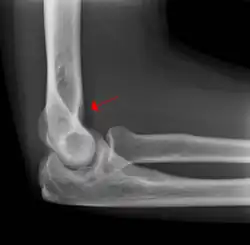

Fat pad sign

The fat pad sign, also known as the sail sign, is a potential finding on elbow radiography which suggests a fracture of one or more bones at the elbow. It may indicate an occult fracture that is not directly visible. Its name derives from the fact that it has the shape of a spinnaker (sail).[1] It is caused by displacement of the fat pad around the elbow joint. Both anterior and posterior fat pad signs exist, and both can be found on the same X-ray.

In children, a posterior fat pad sign suggests a condylar fracture of the humerus. In adults it suggests a radial head fracture.

The fat pad sign is invaluable in assessing for the presence of an intra-articular fracture of the elbow. An anterior fat pad is often normal. However a posterior fat pad seen on a lateral x-ray of the elbow is always abnormal. The patient will be unable to flex their elbow and requires orthopaedic input.[2]

The posterior fat pad is normally pressed in the olecranon fossa by the triceps tendon, and hence invisible on lateral radiograph of the elbow.[3] When there is a fracture of the distal humerus, or other pathology involving the elbow joint, inflammation develops around the synovial membrane forcing the fat pad out of its normal physiologic resting place. This is visible as the "posterior fat pad sign" and is often the only visible marker of a fracture, particularly in the pediatrics population.